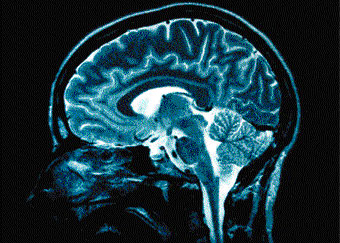

<p>In a study, researchers from Britain’s University College London (UCL) described a technique developed in mice which enabled them to combine information about the function of neurons with details of their connections.<br /><br />The study is part of an emerging area of neuroscience research known as “connectomics”. A little like genomics, which maps our genetic make-up, connectomics aims to map the brain’s connections, known as synapses.<br /><br />By untangling and being able to map these connections —and deciphering how information flows through the brain’s circuits—scientists hope to understand how thoughts and perceptions are generated in the brain and how these functions go wrong in diseases such as Alzheimer’s, schizophrenia and stroke. “We are beginning to untangle the complexity of the brain,” said Tom Mrsic-Flogel, who led the study. “Once we understand the function and connectivity of nerve cells spanning different layers of the brain, we can begin to develop a computer simulation of how this remarkable organ works.”<br /><br />But he said it would take many years of work among scientists and huge computer processing power before that could be done. In a report of his research, Mrsic-Flogel explained how mapping the brain’s connections is no small feat: There are an estimated one hundred billion nerve cells, or neurons, in the brain, each connected to thousands of other nerve cells, he said, making an estimated 150 trillion synapses.<br /><br />“How do we figure out how the brain’s neural circuitry works? We first need to understand the function of each neuron and find out to which other brain cells it connects,” he said. In this study, Mrsic-Flogel’s team focused on vision and looked into the visual cortex of the mouse brain, which contains thousands of neurons and millions of different connections.<br /><br />Using high resolution imaging, they were able to detect which of these neurons responded to a particular stimulus. Taking a slice of the same tissue, the scientists then applied small currents to subsets of neurons to see which other neurons responded and which of them were synaptically connected. By repeating this technique many times, they were able to trace the function and connectivity of hundreds of nerve cells in visual cortex.<br /><br />Using this method, the team hopes to begin generating a wiring diagram of a brain area with a particular function, such as the visual cortex. The technique should also help them map the wiring of regions that underpin touch, hearing and movement.<br /><br />John Williams, head of neuroscience and mental health at the Wellcome Trust medical charity, which helped fund the study, said understanding the brain’s inner workings was one of science’s “ultimate goals”.<br />“This important study presents neuroscientists with one of the key tools that will help them begin to navigate and survey the landscape of the brain,” he said.<br /></p>